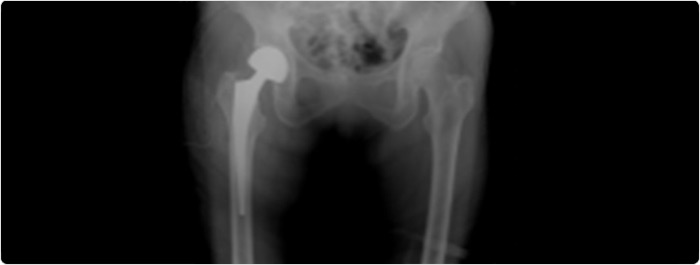

การจำแนกประเภทของกระดูกสะโพกหัก

โดยทั่วไป การเอกซเรย์สะโพกที่ได้รับผลกระทบสามารถให้การวินิจฉัยได้อย่างชัดเจน ควรทำการถ่ายภาพเอกซเรย์ในมุมมองด้านหน้า-หลัง (AP view) และด้านข้าง (Lateral view)

ในผู้สูงอายุที่มีภาวะกระดูกหักแบบเคลื่อนที่หรือภายในข้อ ศัลยแพทย์อาจเลือกทำ “การผ่าตัดเปลี่ยนข้อสะโพกแบบบางส่วน โดยจะเปลี่ยนเฉพาะส่วน หัวกระดูกต้นขา (Femoral head) ด้วยกระดูกเทียมโลหะ แต่จะไม่เปลี่ยนส่วนเบ้ากระดูกสะโพก (Acetabulum)” หรือที่เรียกว่า Hemiarthroplasty โดยเปลี่ยนส่วนของกระดูกที่หักด้วยรากเทียมโลหะ อย่างไรก็ตาม สำหรับผู้สูงอายุที่มีสุขภาพแข็งแรงและยังคงมีการเคลื่อนไหวอย่างคล่องตัว การผ่าตัดเปลี่ยนข้อสะโพกทั้งหมด (Total hip replacement) อาจเป็นทางเลือกที่เหมาะสม ผู้สูงอายุที่สามารถเคลื่อนไหวได้อย่างอิสระและมีภาวะกระดูกสะโพกหักอาจได้รับประโยชน์จากการผ่าตัดเปลี่ยนข้อสะโพกทั้งหมดแทนการผ่าตัดเปลี่ยนข้อสะโพกแบบบางส่วน (Hemiarthroplasty)